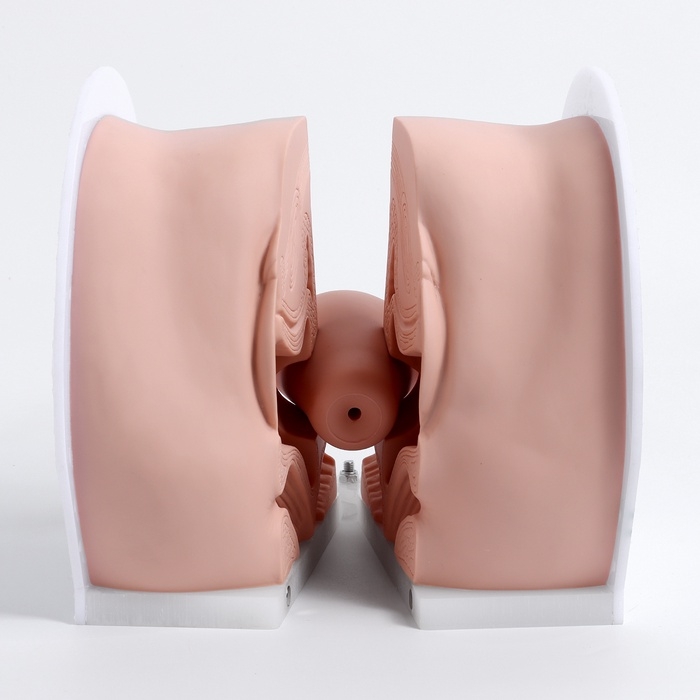

Анатомические модели

ЕКБ 93

No Brand, артикул: 7072363